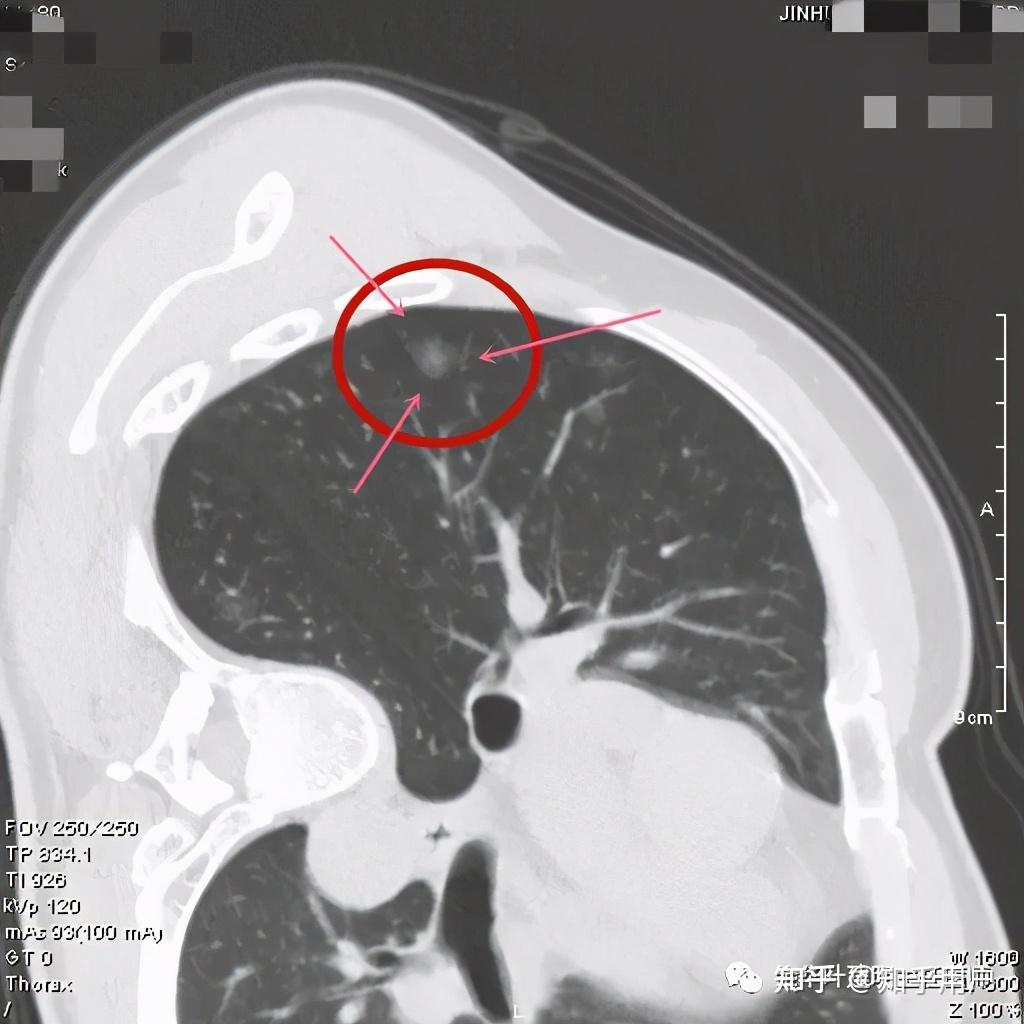

看着,非常不错,以后原位腺癌与非典型增生不是癌了,不需要手术了,至少不能按恶性肿瘤的方式进行手术了。这是好事!但真的到了临床上,如何把握,我看仍是前路漫漫,迷雾重重!我们先举几个例子,来看看影像上如何来区分AAH、AIS、MIA以及浸润性腺癌。下面的四幅CT图分别各是其中的一种,是我们术后有病理依据确诊的病例,你能分出哪张是哪种吗?

有没有高手能分辨出来?我是一头雾水,根本分不清到底哪个是哪种。都是纯磨玻璃结节,都是瘤肺边界清楚,大小都在1厘米左右或以下。现比如下面这四幅CT图也是分别为AAH、AIS、MIA以及浸润性腺癌(贴壁型),你能分得清楚哪幅图是哪种吗?

这几乎就是四胞胎,长的没什么区别,但病理类型天差地别。现在把AAH与AIS剔除出恶性肿瘤后,更是差别巨大了,是癌与非癌的区别了,但没有手术切除病检的情况下,你如何来区分?